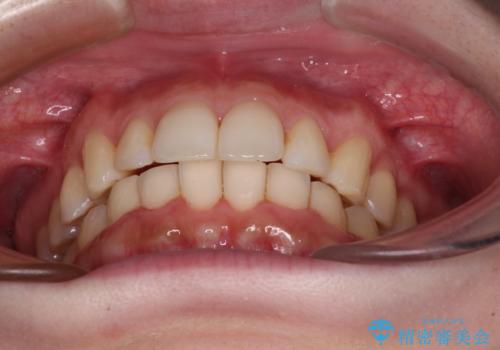

- 上の前歯が出っ張っている気がするとのことで来院された患者様です。

急いで治す必要性がないとのことで、自分のペースでのんびりと治療を行えるインビザラインにて矯正治療を行うこととしました。